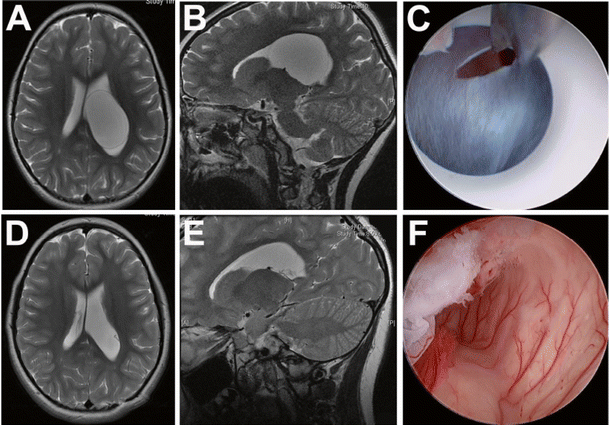

Illustration of the standard right frontal endoscopic approach (a, b) in a 14-year-old male with a history of aqueductal stenosis secondary to a tectal glioma treated by endoscopic third ventriculostomy. After visualization of the floor of the third ventricle (c), an adequate stoma was created with a NeuroBalloon catheter (d) with subsequent ascertainment that no basal cistern membranes were present (e). (Adopted with permission from Guzman et al. [29])